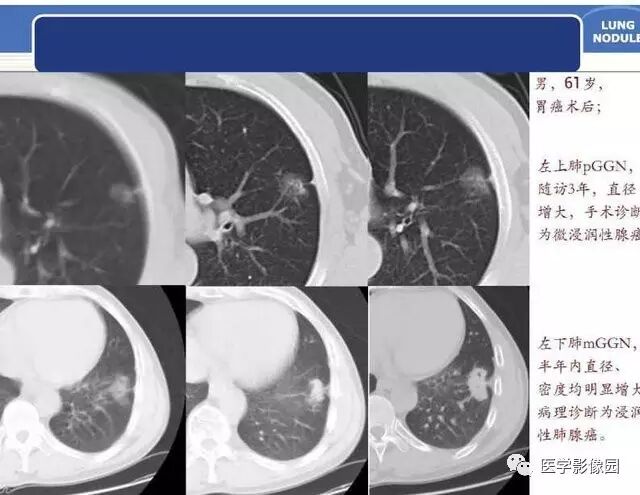

肺磨玻璃结节的CT诊断与临床处理策略